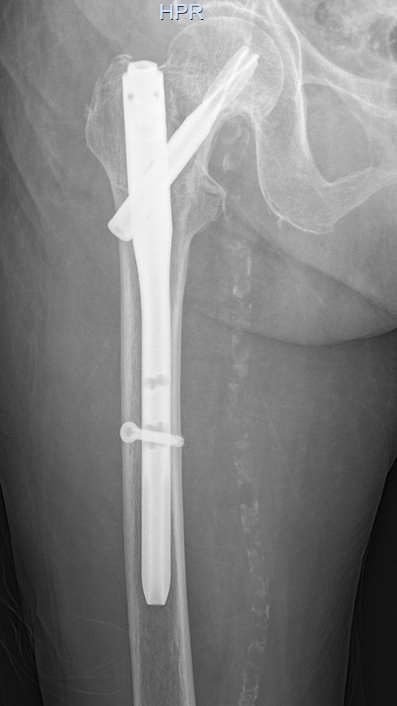

骨科团队迅速评估病情,认为手术治疗是让老人重新站起来的唯一希望,也是降低长期卧床并发症风险的最佳选择。在科主任李忠教授带领下,唐炼副主任医师团队反复研究影像资料,精心设计创伤小、固定可靠的手术方案——微创闭合复位股骨近端防旋髓内钉(PFNA)内固定术。手术仅用时30分钟顺利完成。